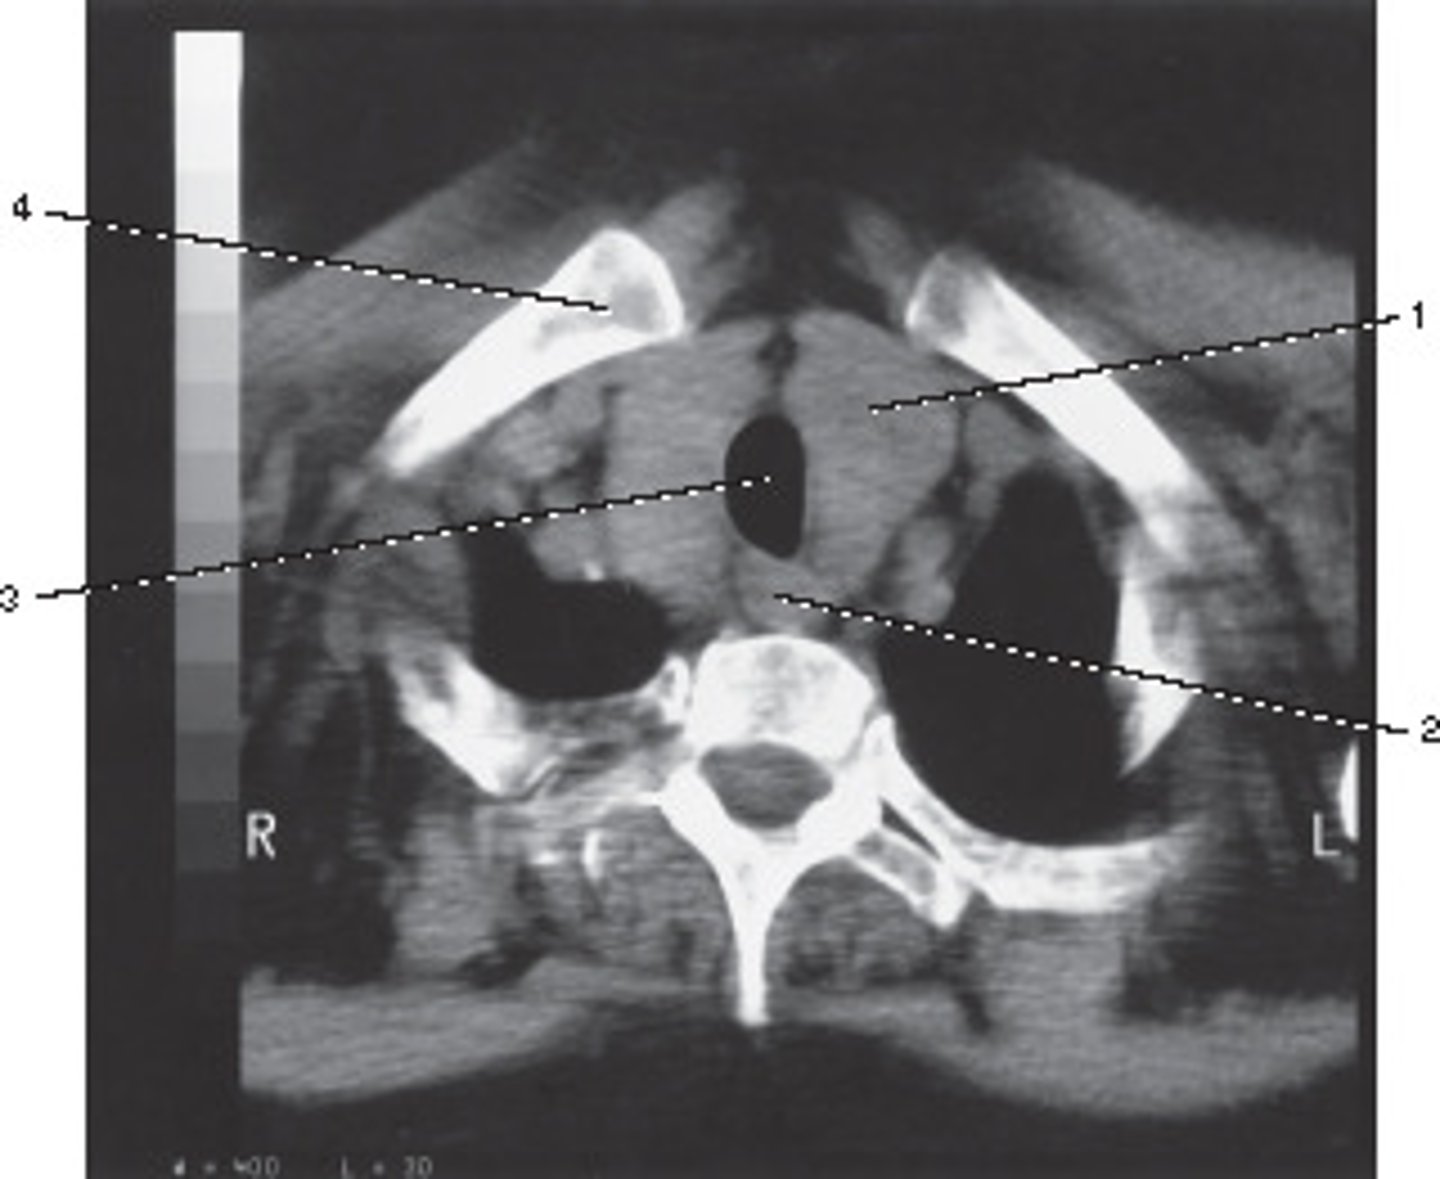

Number 2 corresponds to which of the following?

<p>Number 2 corresponds to which of the following?</p>

Number 4 corresponds to which of the following?

<p>Number 4 corresponds to which of the following?</p>

Number 1 corresponds to which of the following?

<p>Number 1 corresponds to which of the following?</p>

Vertebral Artery

Number 3 corresponds to which of the following?